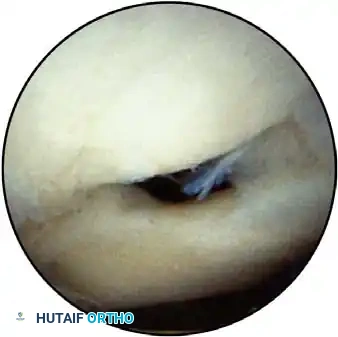

Early identification of micro-instability is paramount. Subtle instability often precipitates superior labral anterior and posterior (SLAP) lesions and secondary rotator cuff impingement. By identifying these lesions early, treatment can be directed at the root biomechanical cause rather than merely the secondary symptoms.

In the overhead throwing athlete, the shoulder is repeatedly placed in extreme abduction, hyperextension, and external rotation (the late cocking phase). This position forces the greater tuberosity and the undersurface of the rotator cuff to impinge against the posterosuperior glenoid rim and labrum. This internal impingement results in fraying of the cuff undersurface and the superior labrum. Repetitive microtrauma leads to anteroinferior ligamentous laxity and a "peel-back" of the posterosuperior capsular complex.

Appropriate surgical intervention relies on a thorough arthroscopic evaluation to decode these complex pathological findings. Diagnostic arthroscopy is also highly indicated for: